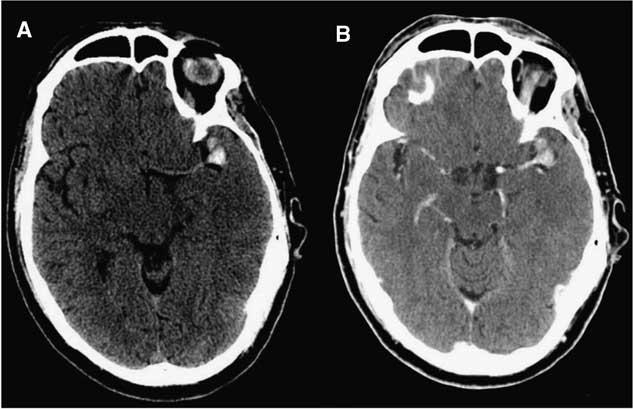

Initial computed tomography (CT) scans demonstrated a thrombosed MCA aneurysm (1.8×1.3×1.0 cm) with associated occlusion of the left MCA at its bifurcation (Figure 1). There was no evidence of subarachnoid hemorrhage or intracerebral blood. There was loss of grey-white differentiation in the left insular, frontal and parietal lobes. The initial Alberta Stroke Program Early CT score was 2, indicating an established stroke with diffuse MCA involvement. As such, stroke mitigation by endovascular or surgical revascularization was not pursued. The next day magnetic resonance imaging (MRI) and MR angiography (MRA) confirmed a large area of ischemic acute infarction in the left MCA territory and extremely poor opacification of distal left MCA branches (Figure 2).

Figure 1 Initial uninfused (A) and infused (B) CT demonstrating hyperdensity at the left MCA bifurcation representing an acutely thrombosed aneurysm with occlusion of the parent vessel and early MCA territory infarction.